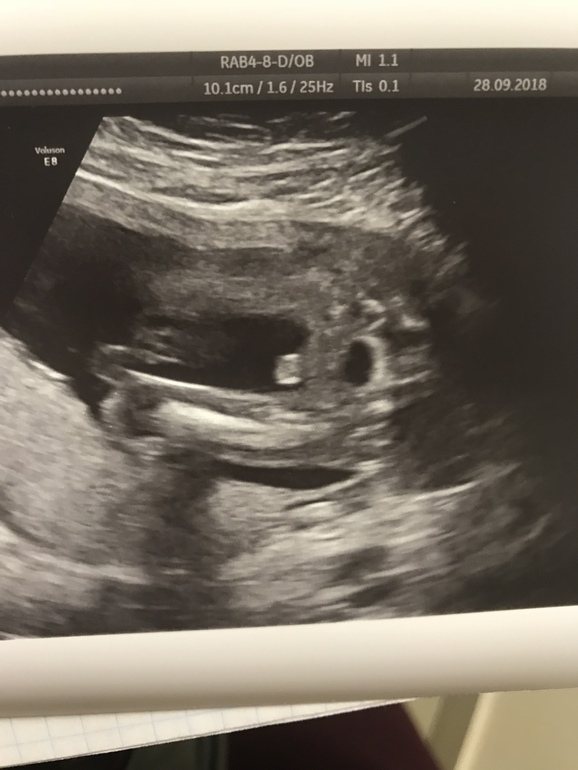

Пол малышаДевочки,всем привет!) Успокойте мою душу😄 Не обманывает ли меня зрение, это же мальчик по узи ??? А то 37 недель и только на одном узи в 25 недель удалось увидеть пол , врач сказала мальчик вроде бы,но хочется мнение со стороны, а то хожу весь срок с сыночком, а родится девочка ,вот неожиданность будет 😄 на втором фото под пуповиной оно самое же ,писюндрик ?)

Так на втором под пуповиной в самом самом низу там торчит ,может на фото просто плохо видно )

Но это не писюнчик))) помоему это пуповина весь кадр закрыла, но и половой расщелины нет))) однозначно это мальчик 😅